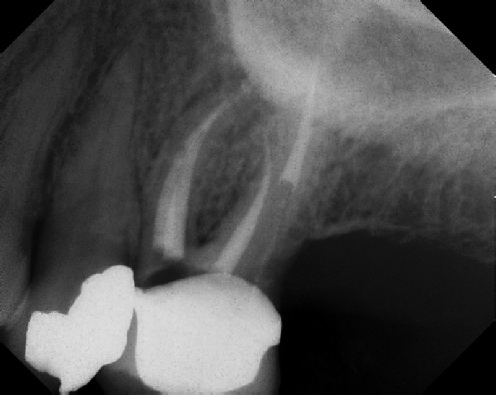

Root Canal Retreatment - Meriden 8 mos. recall Post-op Pre-op